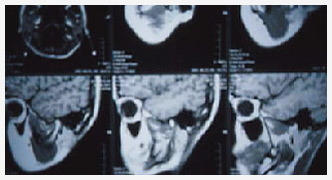

レントゲン画像から読み解く「骨密度レベル」

"BONE RIGHT"は、当院の院長、日本歯科骨粗鬆研究会副理事長である高石佳知博士が取得した国際特許「下顎骨密度(BMD)評価装置と評価方法」に基づき開発されたレントゲン画像から骨密度の具体的な数値を割り出し、評価する"骨密度評価サポートソフト"です。

ビスフォスフォネート(ビスホスホネート)製剤の副作用による顎骨骨壊死の問題および、歯周病治療の経過に対しても、従来は目視のみでしか確認できなかった骨密度が明確になることで、正しく診察することが可能となりました。 また、インプラント手術の際に、骨量を数値と算出することで正確な診断を行う事も出来ます。

高い測定精度・正確性・安全性(被爆線量)・短時間測定・経済効率を実現。レントゲン画像からの下顎骨骨密度の数値化、さらには集積データに基づいた年齢・性別の評価を可能にします。従って、歯周病患者の治療経過に、歯周病患者の早期発見に役立ちます。